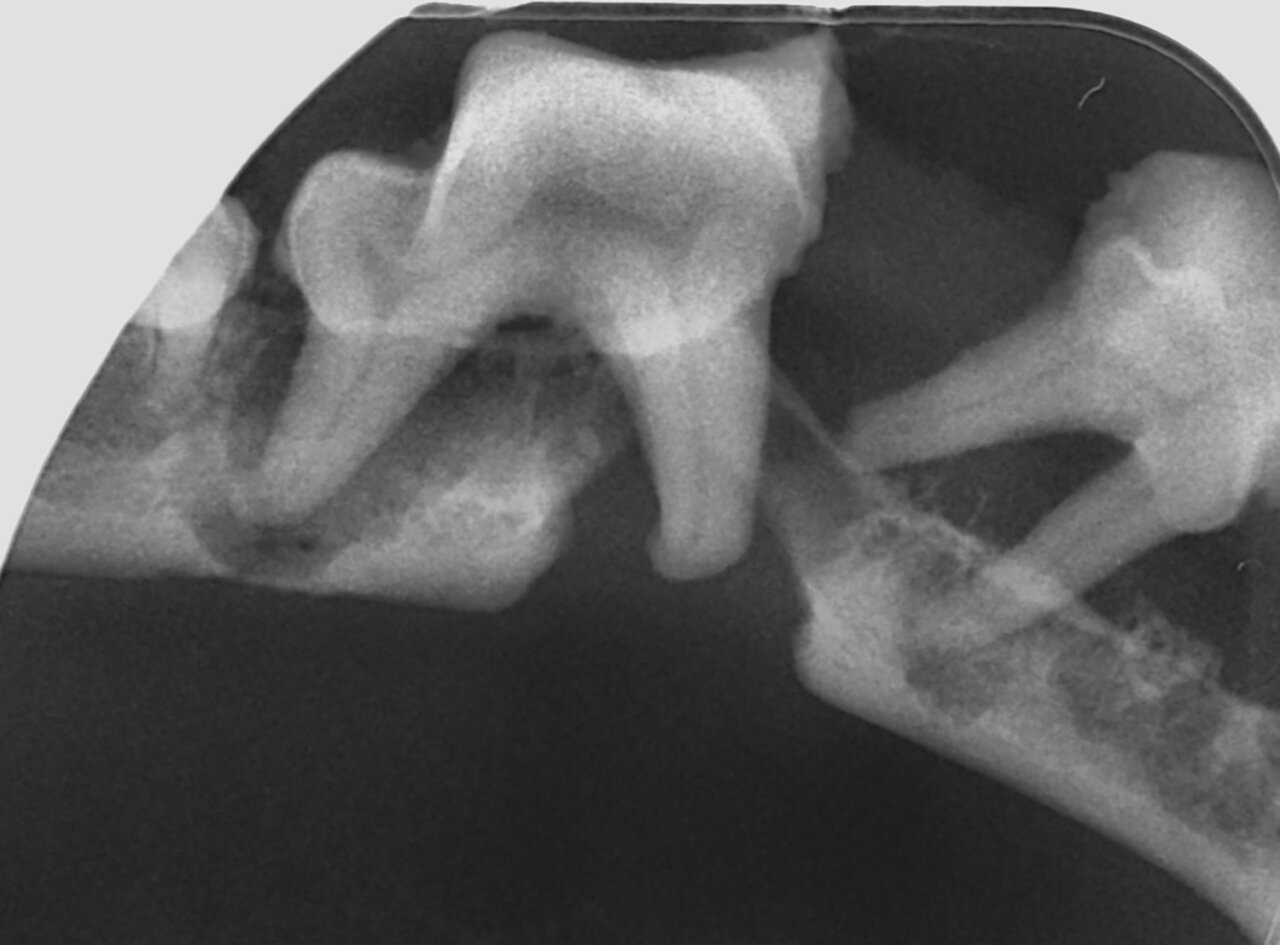

- Grado 2 (PD2): pérdida del soporte óseo menor al 25 % (imagen 7).

- Grado 3 (PD3): pérdida del soporte óseo de un 25-50 % (imagen 8).

- Grado 4 (PD4): pérdida del soporte óseo mayor de un 50 % (imagen 9).

Además de permitirnos evaluar el grado de enfermedad periodontal, también hace posible seleccionar el mejor tratamiento en función de su patología y las posibles complicaciones, como las fracturas mandibulares iatrogénicas en perros de talla pequeña con enfermedad periodontal PD4 (imágenes 10 y 11).